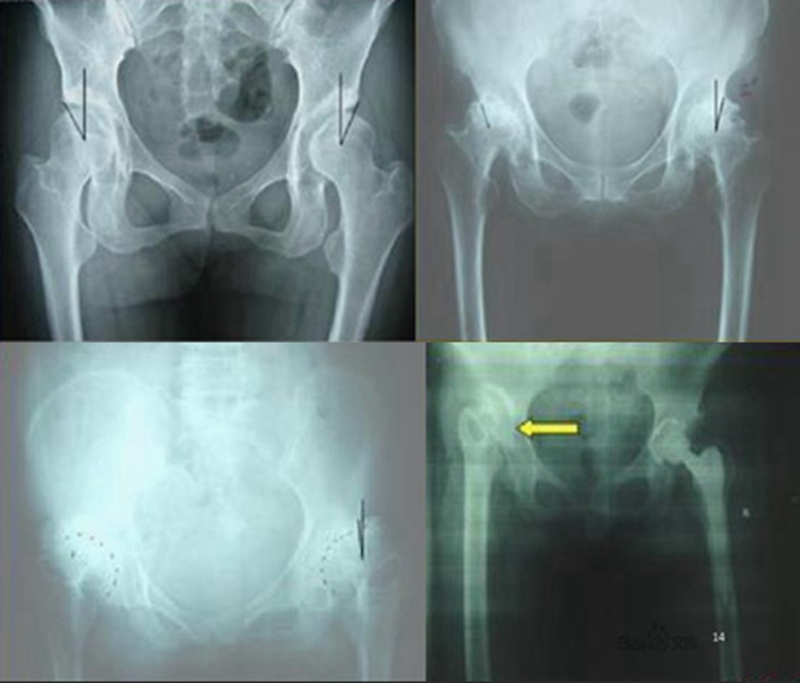

1、Crowe分型

Crowe于1979年提出的分型,能够较好地量化髋关节的半脱位程度,对临床手术决策具有重要的指导意义。其主要依据股骨头移位距离占股骨头高度百分比或者占骨盆高度的百分比进行划分。

Ⅰ型:不全脱位<50%;

Ⅱ型:不全脱位50%-75%;

Ⅲ型:不全脱位75%-100%;

Ⅳ型:不全脱位>100%,即完全脱位。

2、Hartofilakidis分型

Hartofilakidis于1996年提出成人DDH的简化分型方法。根据DDH病变程度的不同,使用三种类型分别对应髋关节发育不良、髋关节半脱位及髋关节脱位三种改变。

Ⅰ型:髋关节发育不良;

Ⅱ型:髋关节低位脱位;

Ⅲ型:髋关节高位脱位。